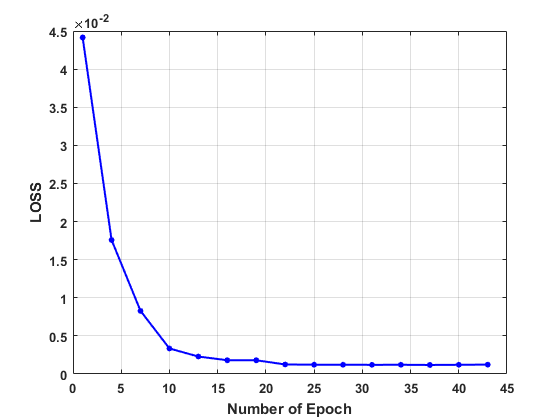

In the first place, we test the effect of the number of epoch on the convergence in network training on the human dataset. The values of the loss function, PSNR, and SSIM are plotted in Fig. 3, which evidence the convergence of our LRIP-net. Accordingly to plots, we fix the number of the epochs as during the training in the following experiments.